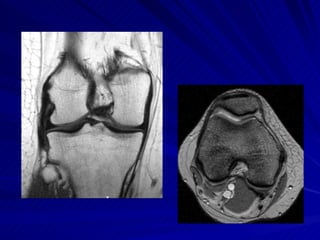

LIGAMENTOS E TENDÕES Tendão do Quadríceps Reto femoral, vasto intermédio, vasto medial e vasto lateral – pólo superior da patela Fusão vasto medial e lateral Ligamento Patelar Pólo inferior da patela – tuberosidade anterior da tíbia

LIGAMENTOS E TENDÕESTendão do Quadríceps Reto femoral, vasto intermédio, vasto medial e vasto lateral – pólo superior da patela Fusão vasto medial e lateral Ligamento Patelar Pólo inferior da patela – tuberosidade anterior da tíbia